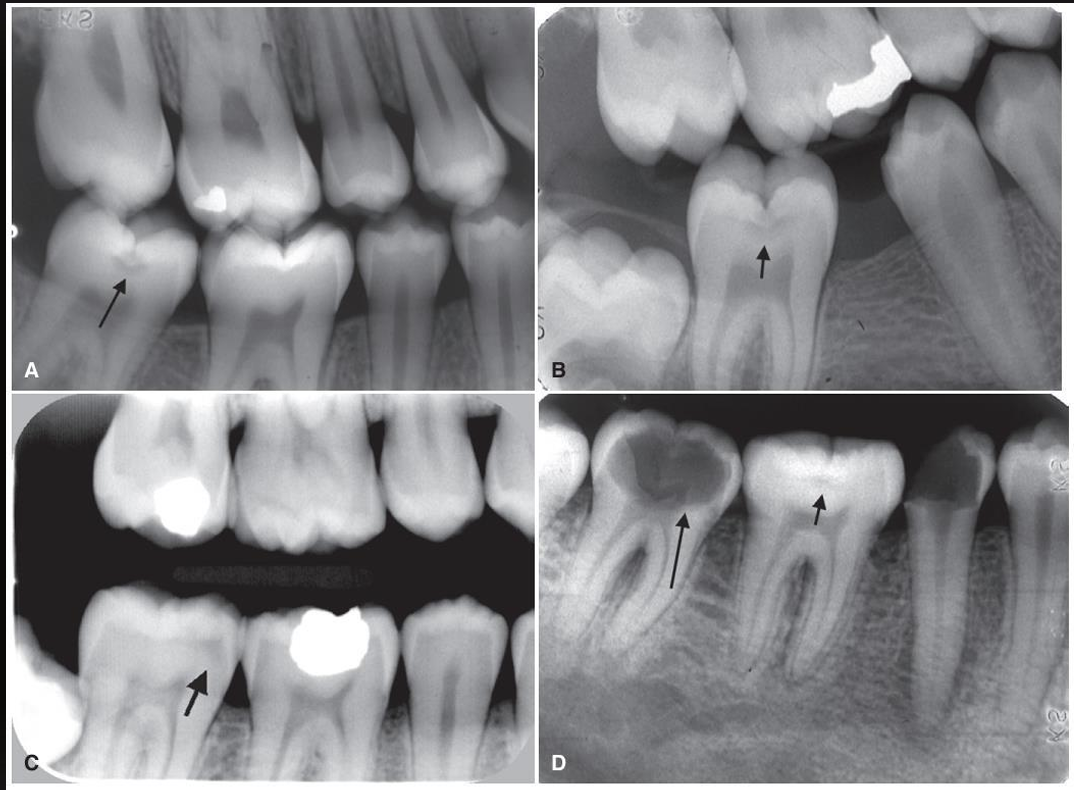

what are these arrows pointing at? (except for 2nd molar in image D)

small occlusal caries